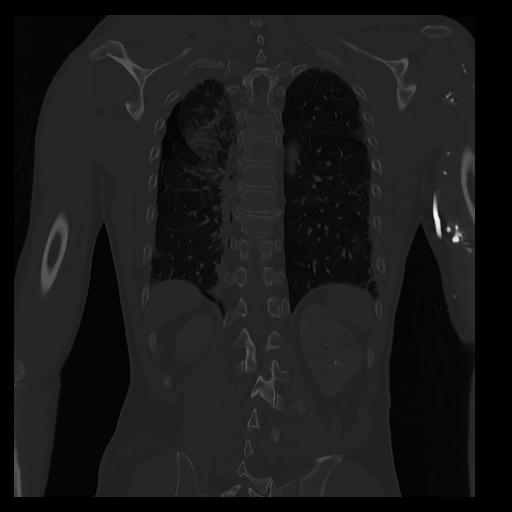

32 PULMON,CE,Coronal,3.000,PULMON,Coronal,